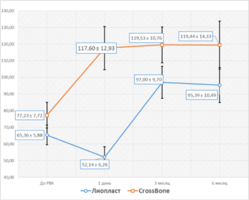

- На всех сроках наблюдения оценивали плотность костной ткани в единицах шкалы Хаунсфильда (HU) в зоне дефекта (HUд).

- Для индивидуальной оценки остеоинтеграции определяли плотность костной ткани в реперной зоне интереса (HUр), которую выбирали в прилежащем к дефекту участке здоровой костной ткани, и расчитывали относительную величину - соотношение HUд/HUp.

Компьютерная томография установила значительные различия в рентгеновской плотности остеопластических материалов «CrossBone»® и «Лиопласт»®.

Деминерализованная спонгиоза «Лиопласт»® является рентгенонегативной. Плотность материала, измеренная в первый день после операции РВК (209,08±25,1) оказалась намного меньше плотности здоровой костной ткани (391,25±28,83).

Плотность «CrossBone»® выше плотности костной ткани.

Соотношение плотности зоны дефекта и реперной области (HUд/HUр) на первый день было равно 1,2±0,11.

Компьютерные томограммы 22 пациентов I группы показали замещение костного дефекта регенерата через 3 месяца после операции: определяется формирующийся трабекулярный рисунок границы костной полости не дифференцируются от окружающих тканей.

Образование новой костной ткани подтверждено результатами измерения плотности костной ткани.

При использовании деминерализованной спонгиозы «Лиопласт»® через 3 месяца уровень поглощения (HU) костной ткани, формирующейся в области дефекта приближается по своему к плотности реперной зоны.

Средний прирост плотности костной ткани у пациентов I группы составил 86% (табл. 1).

Образование новой костной ткани доказывает соотношение плотности операционной области к здоровой костной ткани, которое в первый день после РВК составляло 0,53±0,04. , а к концу третьего месяца его значение увеличилось практически в 2 раза и приблизилось к единице (рис.3).

Через 6 месяцев все показатели оставались неизменными.

На КТ у 21 пациента II группы на всех сроках наблюдения отчетливо видны гранулы материала, которые не были подвержены резорбции.

Показатели плотности операционной зоны через 3 и 6 месяцев после РВК при применении материала «CrossBone»® схожи с первым днем после операции (рис.3).

Отношение плотности в операционной области к здоровой костной ткани (HUд/HUp) также остается выше 1,0 (табл. 1).

Рис. 3. Изменение плотности костной ткани в области дефекта на следующий день после операции РВК, через 3 и 6 месяцев.